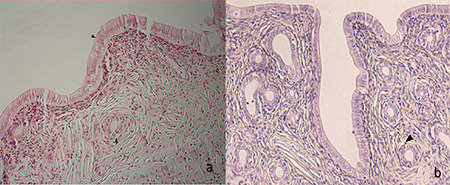

Results: Despite the lack of a meaningful distinction in the quantity of primordial and primary follicles between the two groups, a substantial disparity was observed in the overall follicle count and AMH levels. Specifically, the intervention group exhibited significantly lower total follicle counts and AMH levels than the control group (p≤0.001). The researchers also found that the endometrium of ethanol-treated rats was significantly thinner than that of control rats (p≤0.001).

Conclusion: This study concluded that ethanol consumption can negatively affect reproductive ability and the success of in vitro fertilization treatment by reducing ovarian reserve and thinning the endometrium.